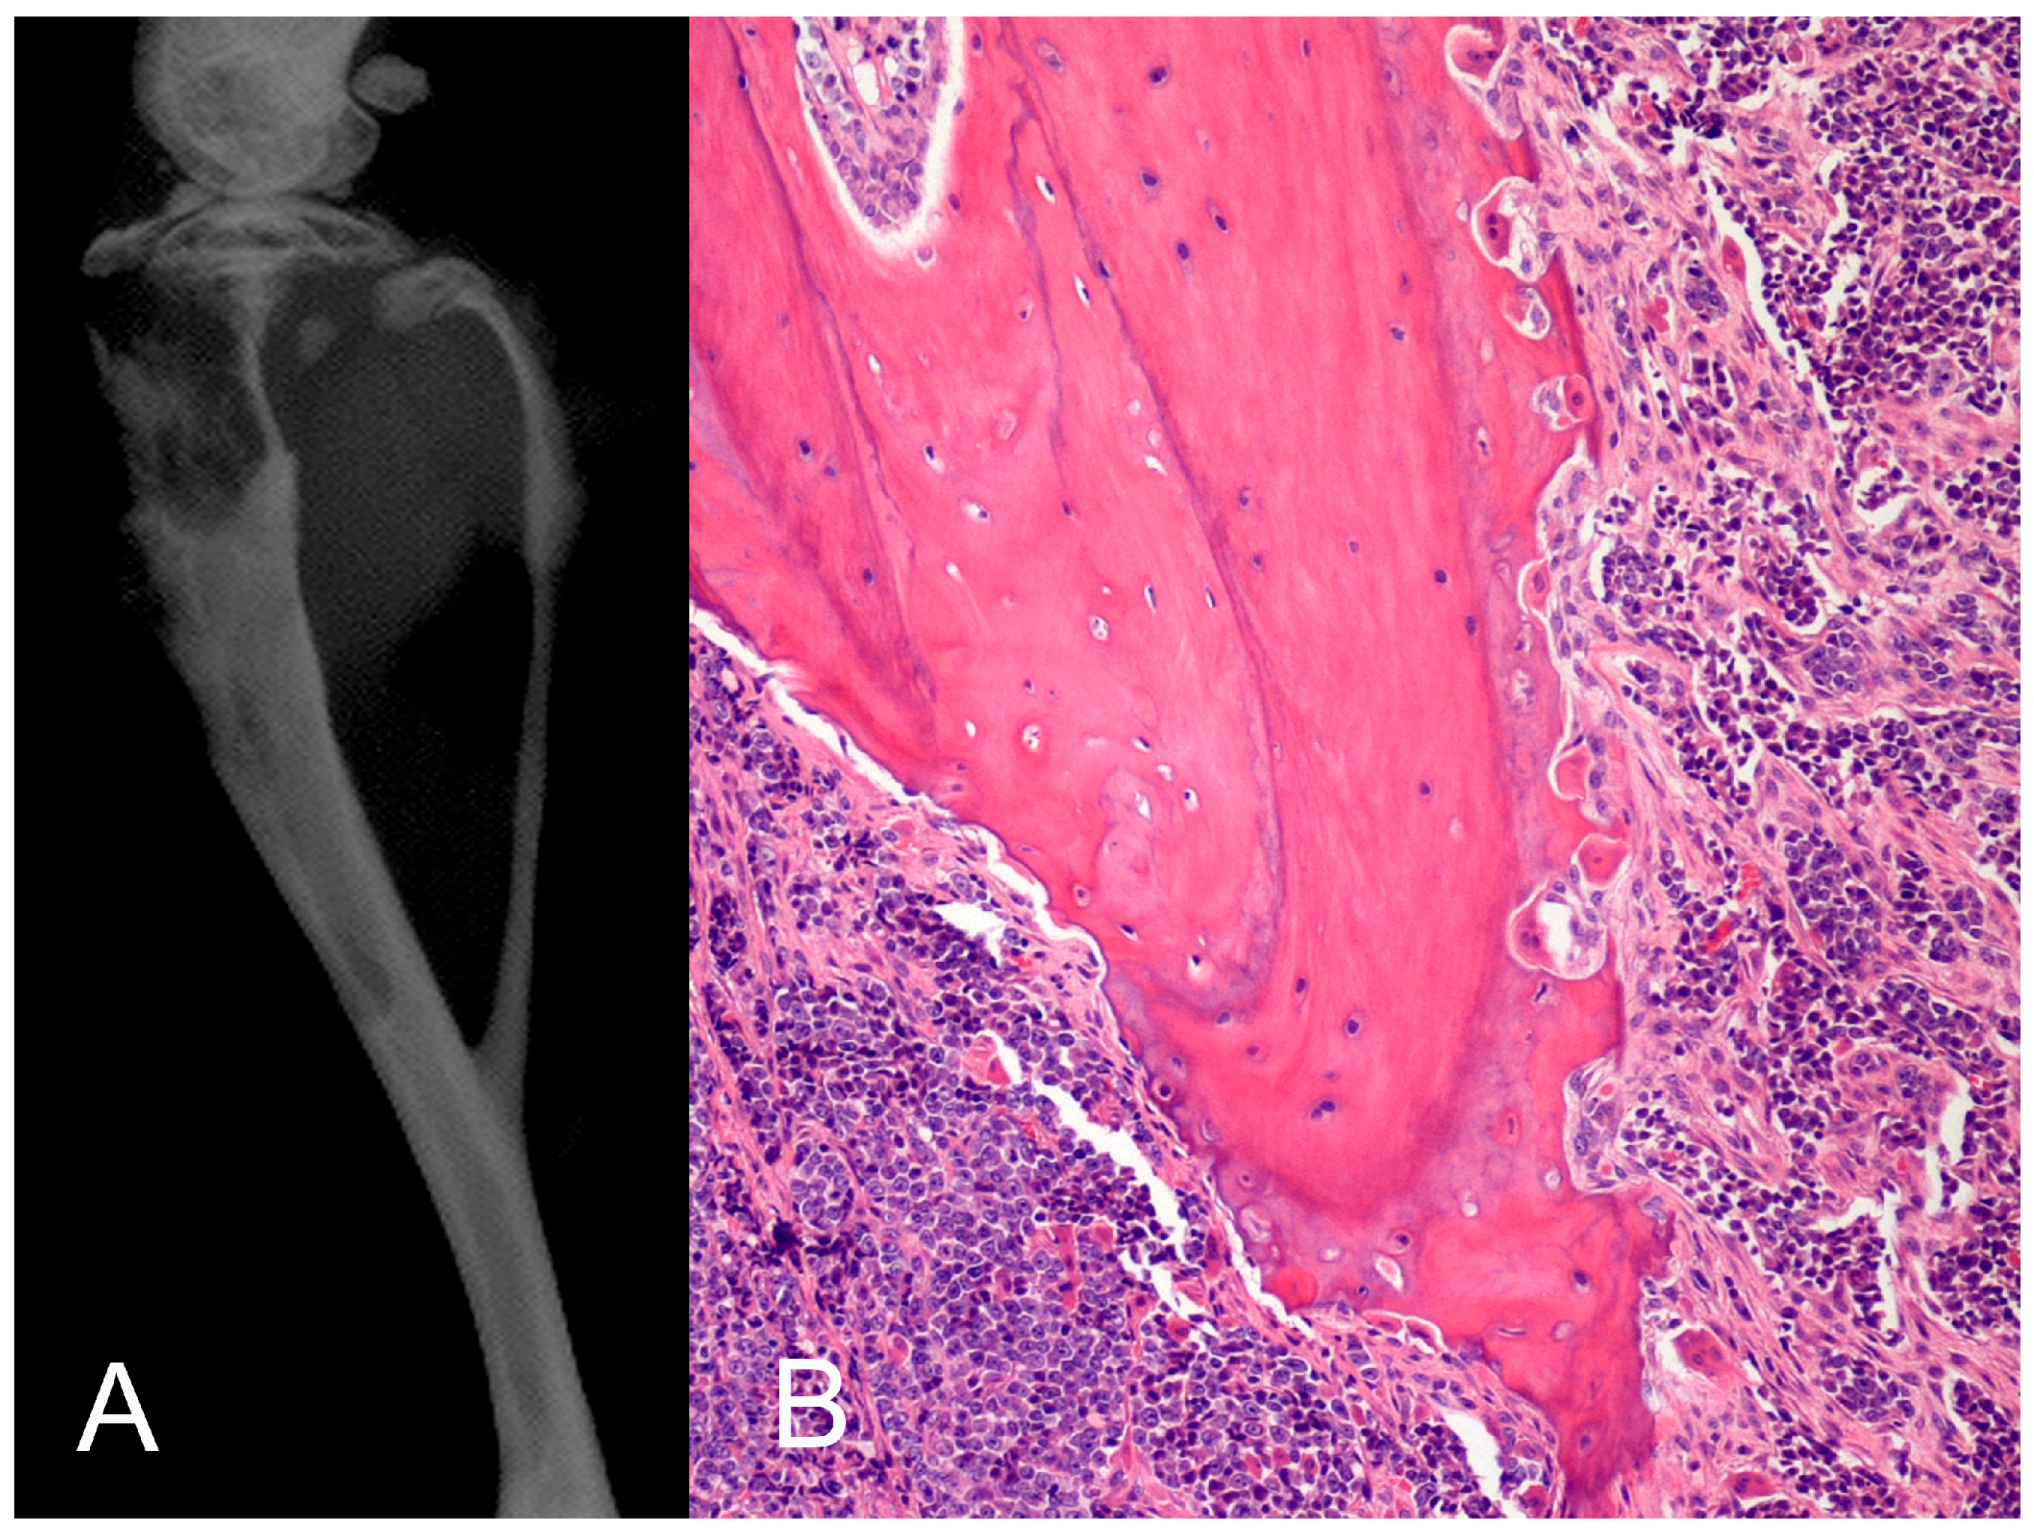

- Supsavhad, W.; Dirksen, W.P.; Martin, C.K.; Rosol, T.J. Animal models of head and neck squamous cell carcinoma. Vet. J. 2016, 210, 7–16. [Google Scholar] [CrossRef] [PubMed]

- Martin, C.K.; Dirksen, W.P.; Shu, S.T.; Werbeck, J.L.; Thudi, N.K.; Yamaguchi, M.; Wolfe, T.D.; Heller, K.N.; Rosol, T.J. Characterization of bone resorption in novel in vitro and in vivo models of oral squamous cell carcinoma. Oral Oncol. 2012, 48, 491–499. [Google Scholar] [CrossRef] [PubMed]

- Martin, C.K.; Tannehill-Gregg, S.H.; Wolfe, T.D.; Rosol, T.J. Bone-invasive oral squamous cell carcinoma in cats: Pathology and expression of parathyroid hormone-related protein. Vet. Pathol. 2011, 48, 302–312. [Google Scholar] [CrossRef] [PubMed]